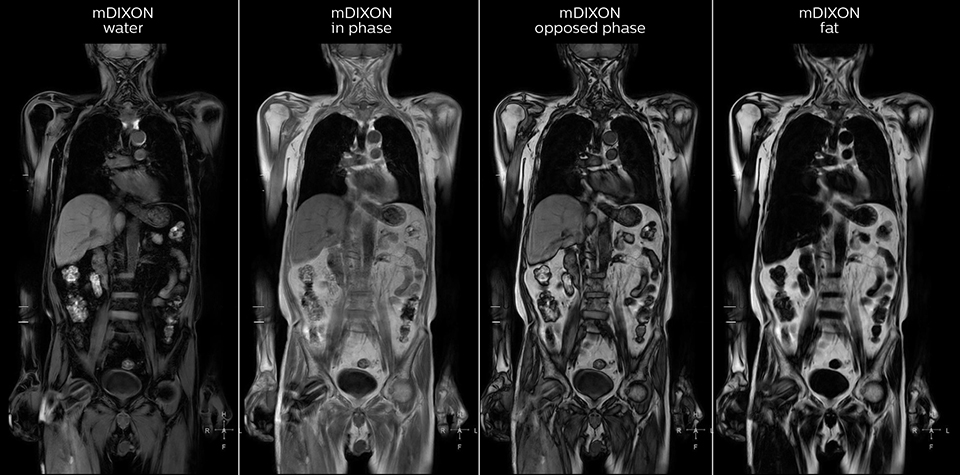

Kawasaki Sawai Hospital’s whole body protocol also includes an mDIXON FFE sequence. Because mDIXON provides images for four contrast types – water only, fat only, in-phase and out-of-phase – from a single acquisition, it is useful in many ways.

“mDIXON FFE allows us to quickly get information we need to assess the presence of fat. That gives us more information when we need to diagnose bone lesions, and when we are asked to judge fat-containing lesions such as hepatocellular or renal carcinoma,” Dr. Nobusawa says. “The mDIXON fat images can help us to differentiate fatty bone marrow from bone lesions. This is especially useful in elderly people, who tend to have fattier bone marrow. The water images provide a high signal-to-noise ratio in the intestinal canal, which is valuable for visualizing lesions in the colon,” he says.